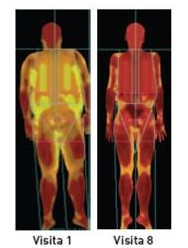

“Nova abordagem para o tratamento da obesidade: Estudo Prokal, resultados do Método PronoKal a 12 e 24 meses” é o tema através do qual serão apresentadas as evidências de que uma perda de peso rápida não é sinónimo da sua rápida e maior recuperação. Pelo contrário, os dados do Estudo Prokal corroboram o que algumas investigações recentes já mostravam: que uma perda de peso rápida inicialmente é um bom indicador de melhores resultados a longo prazo e uma alternativa segura para aqueles que sofrem de obesidade.

Segundo o estudo publicado na revista científica ‘Endocrine’, após 2 anos, o Método PronoKal (www.pronokal.com) ajuda a eliminar mais do dobro da quantidade de quilos, em comparação com dietas hipocalóricas (-12,5Kg vs. 5,2Kg, respetivamente), revelando-se uma alternativa eficaz à intervenção cirúrgica. Estes e outros dados serão apresentados na intervenção do Dr. Jordi Schlaguecke, no dia 17, às 10h00.

O Método PronoKal é um tratamento médico baseado numa dieta proteinada que através de um processo que culmina na reeducação alimentar, permite perder peso rapidamente de forma eficaz. Os pacientes são acompanhados por uma equipa multidisciplinar composta por nutricionistas, técnicos de atividade física e profissionais de coaching, além do médico que os apoia durante todo o processo.